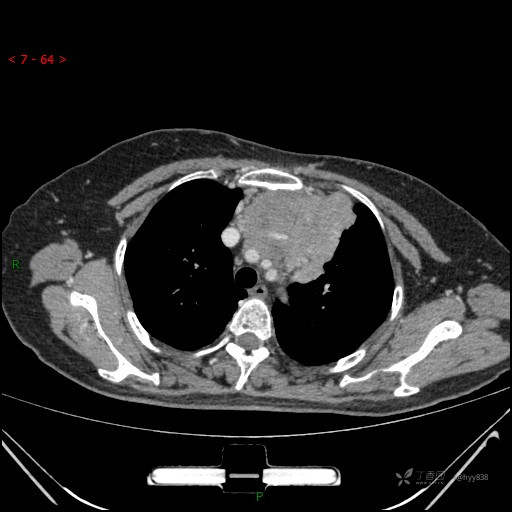

简要病史:患者诉3月余前患新冠肺炎,出现持续性胸闷,活动后可缓解,无胸前区压榨感,无畏寒发热不适,无胸痛咯血、呼吸困难,无恶心、呕吐,无腹痛、腹胀、腹泻等不适,未予以重视,未行特殊处理。患者胸闷持续存在,为进一步诊治,3天前于本院查胸部CT提示前纵膈团块状软组织密度影,肿瘤性病变可能,心包积液,左上肺磨玻璃结节,右下肺增殖灶可能建议进一步检查。门诊以“前纵膈占位” 收入我科。 患者本次起病来精神、食欲、睡眠尚可,大小便正常,体力、体重无明显变化。

辅助检查:CT

动脉期

静脉期